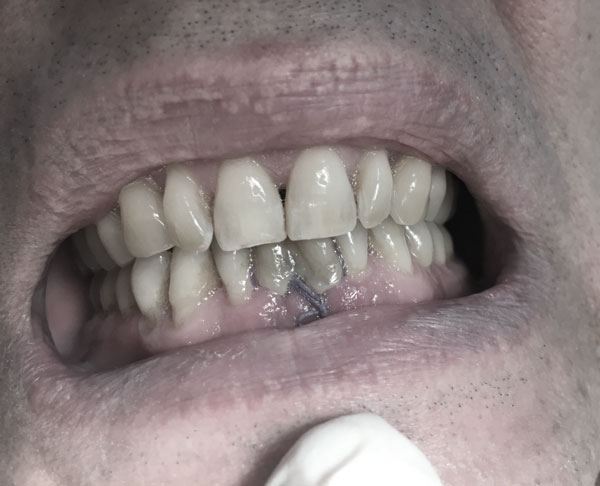

Рис.5 Эстетический результат через полчаса после экстракции зубов 31, 41 и замещением их имплантатами на временных коронках.

Обязательной тактикой немедленной имплантации следует считать атравматичную экстракцию зубов во фронтальном отделе, которая производится с помощью тонких элеваторов. Осуществление люксации при данном оперативном подходе возможно только   с медиальной, дистальной и оральной стенок альвеолы во избежание перфорации вестибулярной стенки апикальной частью имплантата (Рис.1). Даже при остеоинтеграции имплантата при повреждении вестибулярной стенки эстетика будет нарушена. Поэтому после проведения немедленной имплантации 3D-томография снова является идентификатором показателей инклинации имплантата, глубины его погружения в губчатый слой, выявления дефектов костной структуры (Рис.2,3,4,5,6).